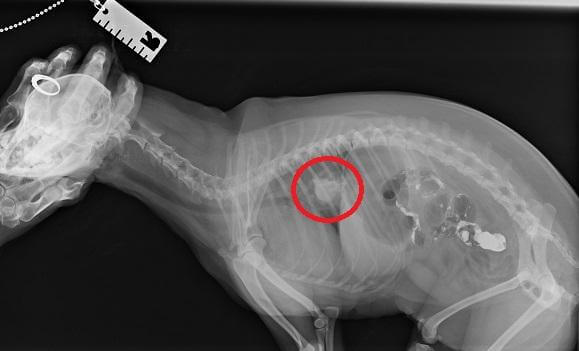

• It happens that small fragments of bones are collected in the stomach into a dense conglomerate, which cannot be expelled from the dog’s body by natural means. Cleansing enema, oil rectal suppositories, and in more complex cases, surgical surgery will help alleviate the condition.